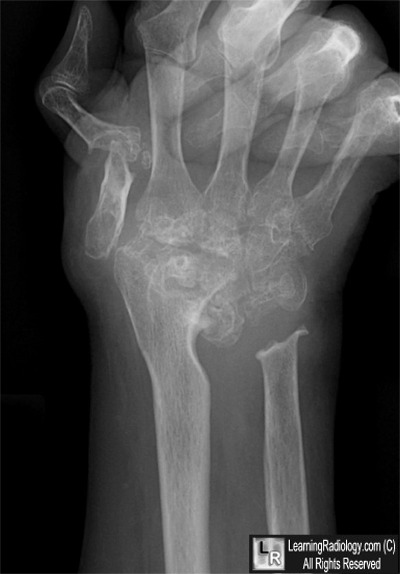

Case of the Week 545

What is the most likely diagnosis?

• 51 year-old female with wrist pain

Frontal view of right wrist

4. Rheumatoid Arthritis

Rheumatoid Arthritis